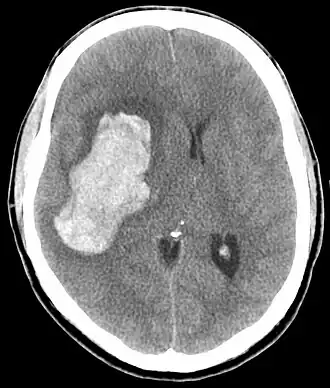

TC de uma hemorragia intracraniana, uma possível complicação de uma emergência hipertensiva.

Emergência hipertensiva é a pressão sanguínea muito alta, geralmente uma sistólica acima de 180mmHg, que resulta em dano ao órgão.[4][6] Isso pode incluir derrame, encefalopatia hipertensiva, síndrome aórtica aguda, síndrome coronária aguda, doença na retina, problemas nos rins, falência cardíaca, edema pulmonar ou pré-eclâmpsia.[3]